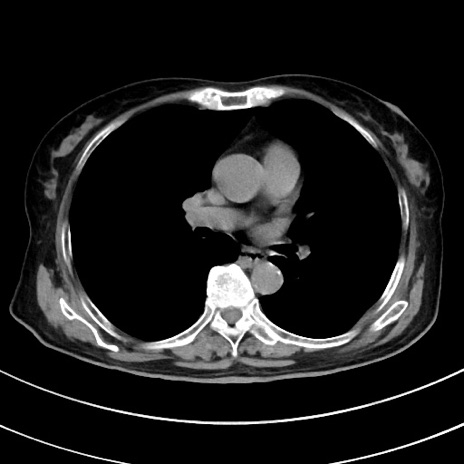

症例33(横断像)

【症例】70歳代 女性

【主訴】心窩部痛

【現病歴】延髄病変の精査・加療にて神経内科入院中。本日より心窩部痛あり。

【身体所見】右下腹部を中心に圧痛と反跳痛あり。

【データ】WBC 10900、CRP 0.02